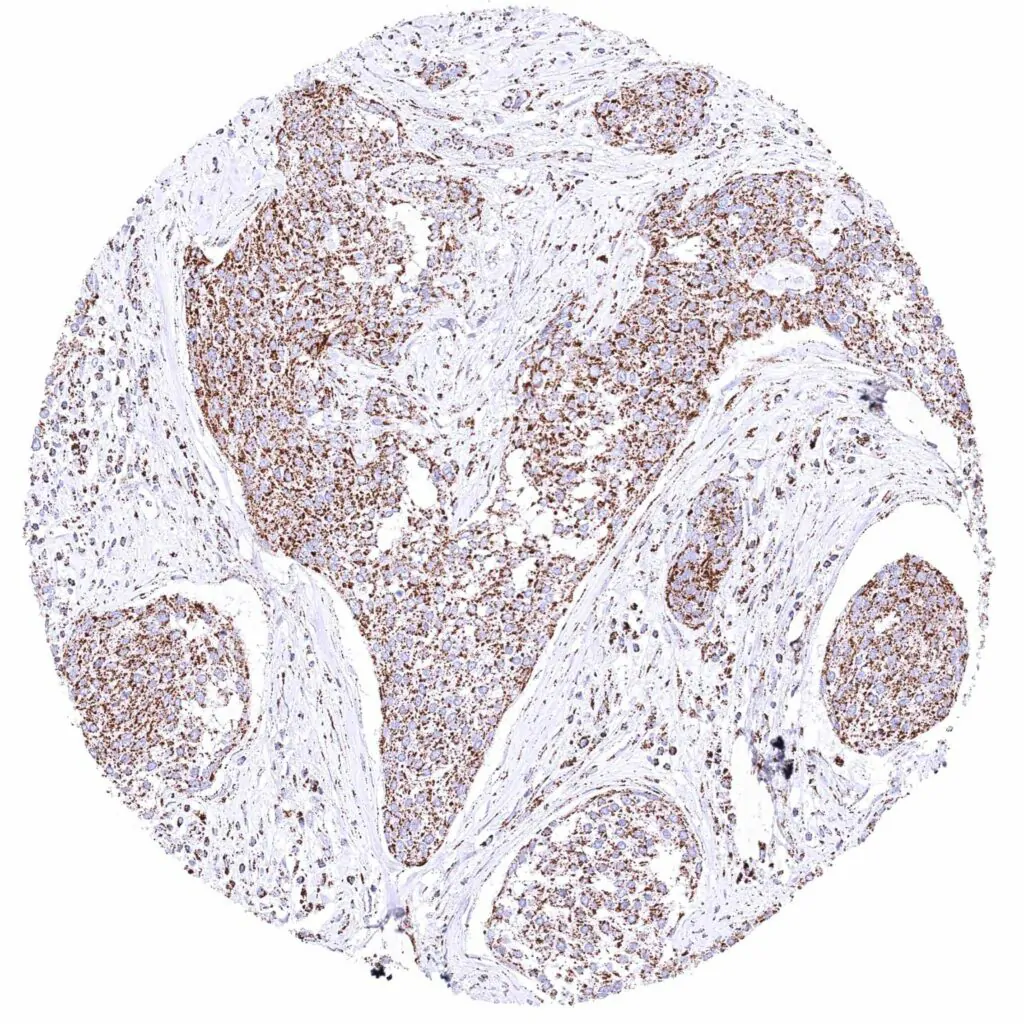

Lymph node – Diffuse large B-cell lymphoma with intense cytoplasmic ATP5J positivity of all tumor cells.